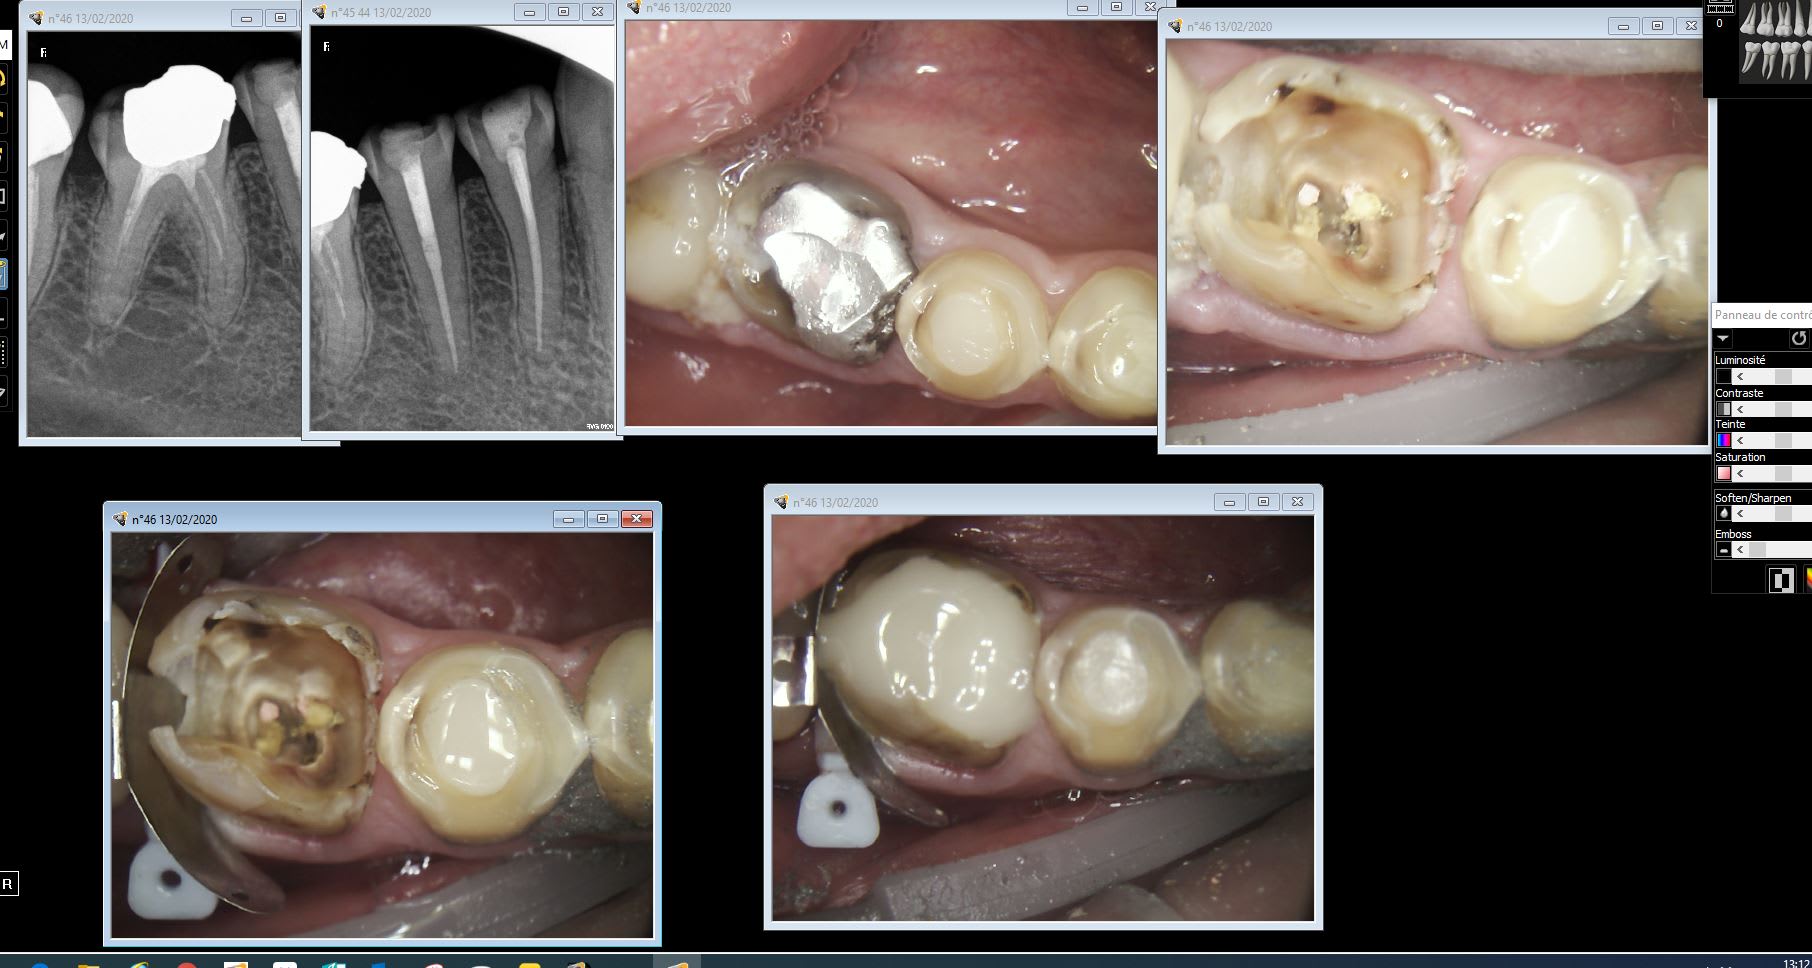

Pas rte vdq0no - Eugenol

Pubg2 rjl8jc - Eugenol

lemondestvaste

13/02/2020 à 13h44

Sérieux Chicot t as fait le compo tenon sans faire le rte ?

Capture d  cran 2015 03 12 12.28 - Eugenol

chicot29

13/02/2020 à 13h59

Pas de tenon.